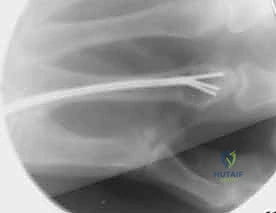

1. التثبيت باستخدام الأسلاك الدقيقة (K-wires)

تُعد هذه الطريقة (Percutaneous Pinning) من التقنيات طفيفة التوغل. يتم إدخال أسلاك معدنية رفيعة جداً عبر الجلد لتثبيت العظم المكسور تحت توجيه الأشعة السينية المستمرة (C-arm) داخل غرفة العمليات.

* الميزة: جروح صغيرة جداً، تعافٍ أسرع للأنسجة الرخوة.

* الإزالة: غالباً ما يتم إزالتها في العيادة بعد 4-6 أسابيع بدون الحاجة لتخدير كامل.

خطوات التثبيت الجراحي - توثيق بصري (Intraoperative Imaging)

يحرص الدكتور هطيف على توثيق خطوات العمل الجراحي لضمان أعلى مستويات الدقة. نستعرض هنا مجموعة من الصور من داخل غرفة العمليات توضح مدى تعقيد ودقة هذه الجراحات:

تتطلب الجراحة انتباهاً خاصاً للأوتار الباسطة والقابضة والأعصاب الدقيقة المحيطة بالعظام. استخدام تقنيات الجراحة الميكروسكوبية (Microsurgery) يضمن عدم الإضرار بهذه الأنسجة الحساسة.

3. التثبيت باستخدام المسامير النخاعية (Intramedullary Nails/Wires)

في بعض كسور عنق العظمة المشطية (مثل كسر الملاكم)، يمكن إدخال سلك أو مسمار مرن داخل النخاع العظمي. هذه التقنية ممتازة للحفاظ على طول العظمة وتصحيح الزاوية دون الحاجة لفتح جراحي كبير.